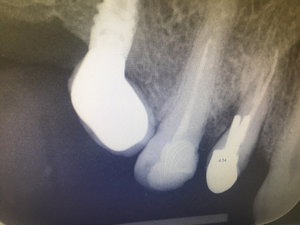

Здравствуйте. Возможно ли спасти зуб (со штифтом), поставить коронку?

От зуба остался маленький клочок. Снимок прилагаю.

Добрый день. Зуб спасти можно, диагноз периодонтит. Для лечения необходимо извлечь штифт, перелечить каналы и далее установить культевую вкладку и затем коронку.